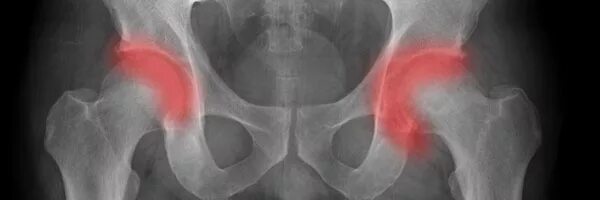

Коксартроз тазобедренного сустава 1 2